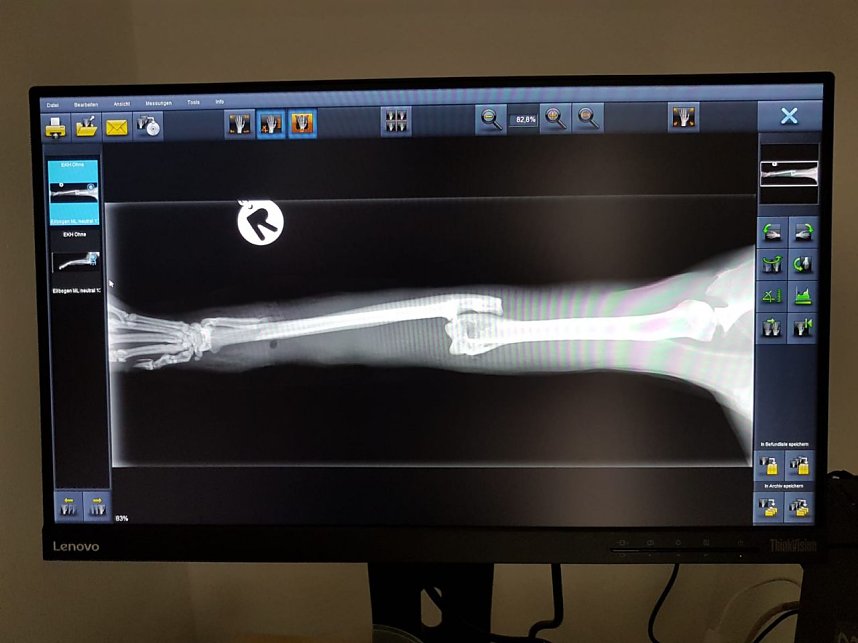

Katze in Schlagfalle gefangen (Foto: S. Dietzel)